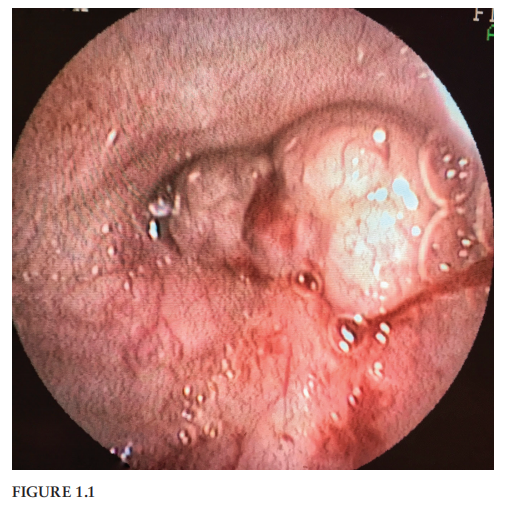

翻译:祁海丽;校对:石慧10 Figure 10.1 presents an endoscopic view of the greater curvature ...